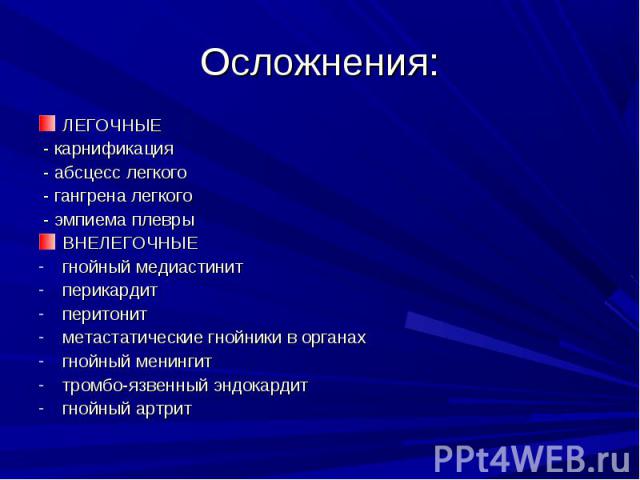

Медицинская тема: легочные осложнения при пневмонии